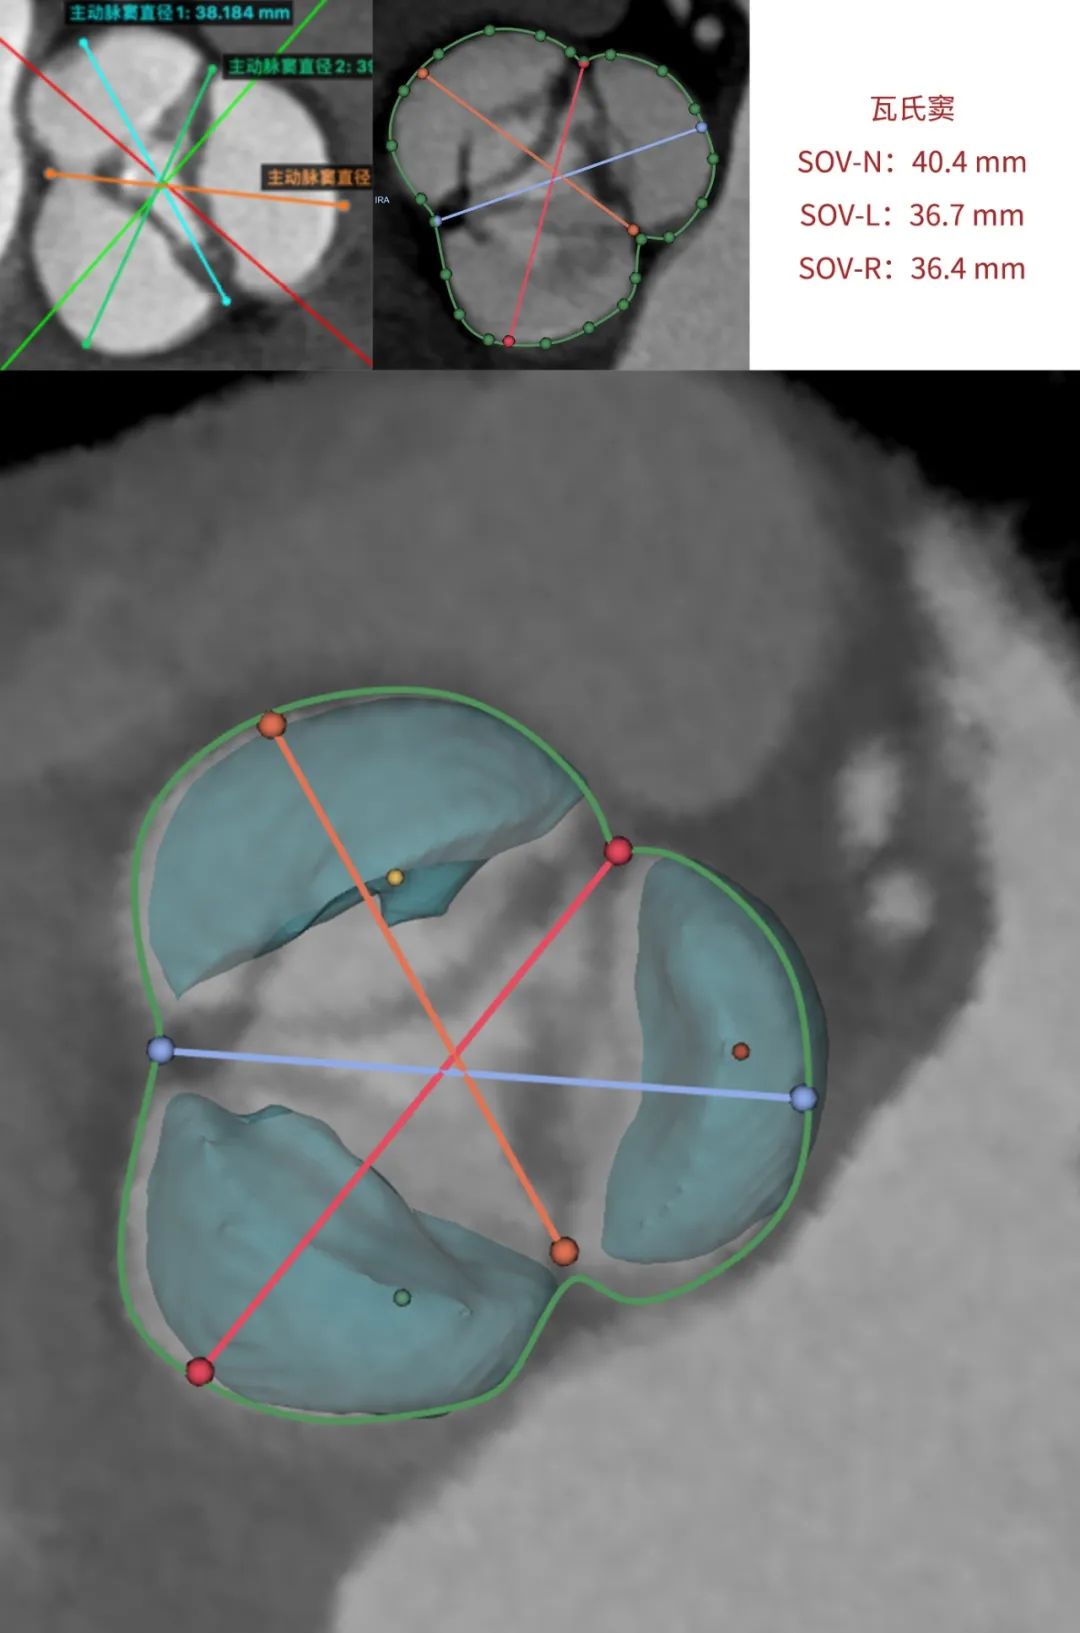

临床团队同时使用了基于医生手工描点的围术期影像评估软件和基于人工智能的瓣膜疾病围术期分析辅助决策软件进行术前影像学评估。

通过术前测量,对病例深入分析,结合人工智能术前分析辅助决策软件进行三维和二维图像融合,郭应强教授指出本例手术存在以下难点: